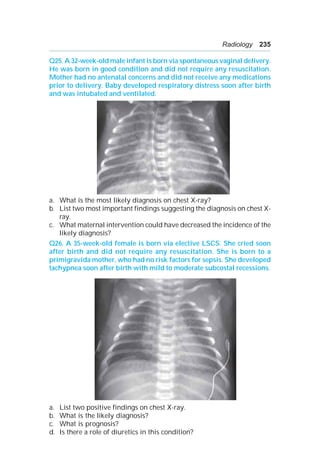

Q30. This 12-year-old presents in pediatric OPD with respiratory distress

of one day duration. He was reviewed in the OPD two days back with

complaint of cough and cold and was diagnosed to have viral URI.

a. What is the most likely diagnosis?

b. How would you confirm the diagnosis?

238 OSCE in Pediatrics

Q31. Given below is the X-ray of a 12-year-old female who presented to